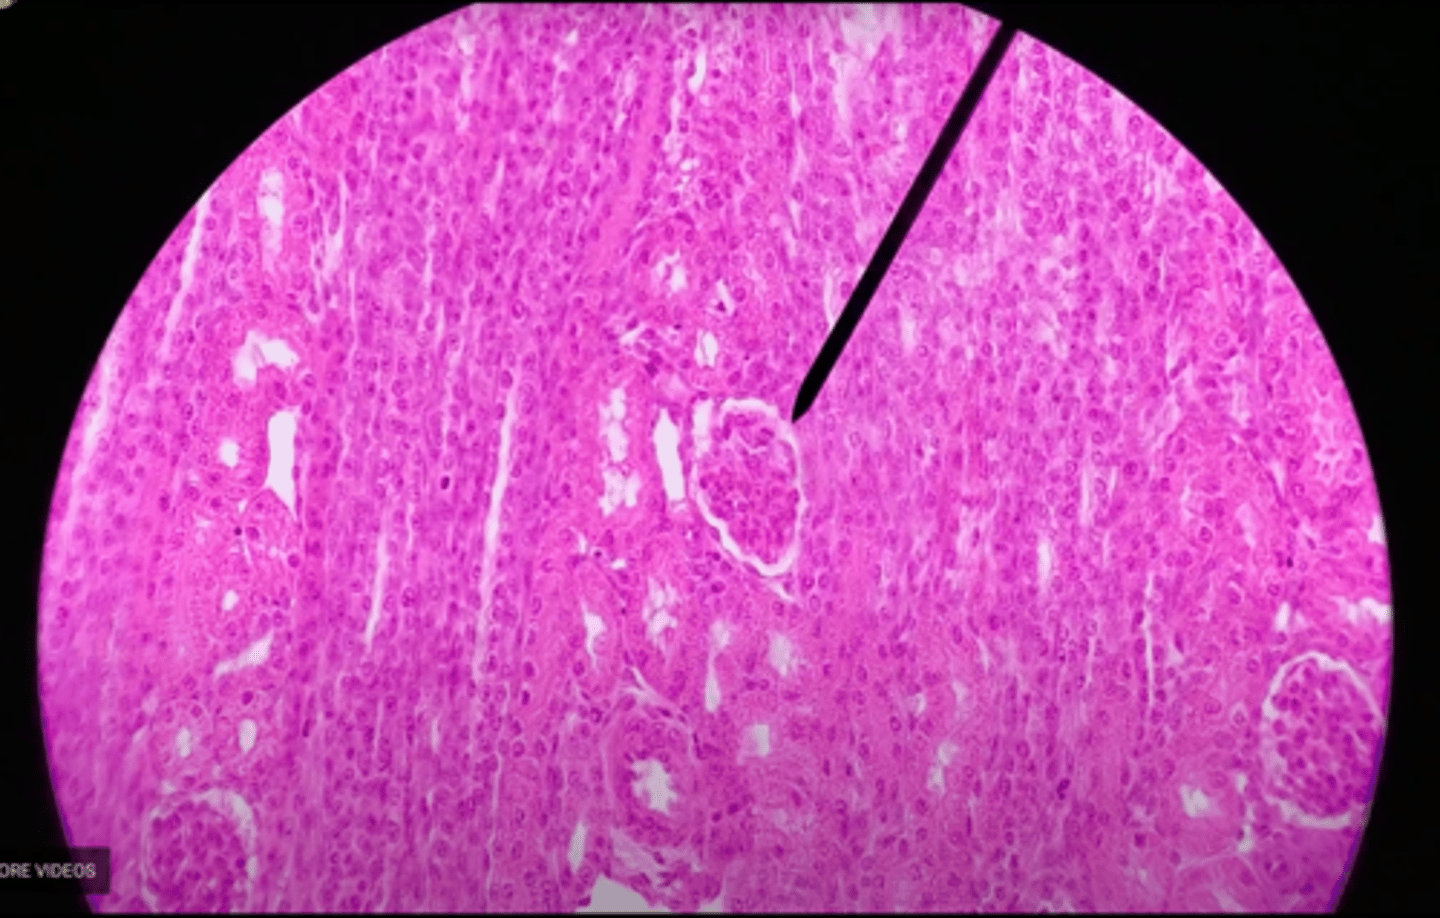

cortex

nephron

the functional unit of the kidney